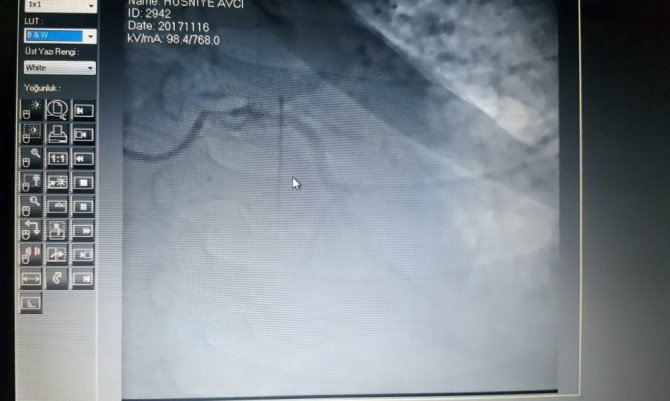

Balıkesir'de 2009 yılında tıp fakültesi hastanesinde safra kesesi ameliyatı geçiren Hüsniye Avcı, ikamet ettiği İstanbul'da rahatsızlanarak 2017 yılının Kasım ayında özel bir hastaneye kaldırıldı. Kalp krizi nedeniyle gittiği hastanede röntgeni çekilen Avcı'nın kalbinde 3 buçuk santim uzunluğunda bir iğne olduğu saptandı. Eşinin hayatında başka hiçbir ameliyat geçirmediğini söyleyen Cemil Avcı, "Eşim 2009 senesinde Balıkesir Tıp Fakültesinde safra kesesi ameliyatı geçirdi. Başka da bir ameliyat geçirmedi. Daha sonra İstanbul'da ikamet ettiğimizden dolayı İstanbul'da bir rahatsızlığından dolayı hastaneye kaldırdık. Hastanede yapılan tetkikler neticesinde kalbinde 3 ya da 4 santim uzunluğunda bir cisim tespit edildi. Daha sonra bu cismin iğne olduğu söylendi" dedi.

Balıkesir Üniversitesi Kalp Damar Cerrahisi Ana Bilim Dalı Başkanı Yrd. Doç. Dr. Orçun Gürbüz, raporunu incelediği hasta ile ilgili olarak, "Hastanın tomografisini göremedim sadece raporunu gördüm. Raporda da maalesef iğne ile alakalı bir şey yazılmamış. Ama anjiyosunda hareket eden metal bir cisim var 3-4 santim uzunluğunda. Bu iki yolla gitmiş olabilir. Eğer tomografiyi görseydim kesin bir şey söyleyebilirdim. Eğer kalbin içindeyse, bu damar yoluyla ilerlemiş olabilir. Herhangi bir kateter takılırken veya bir enjeksiyon yapılırken iğne kırılıp gitmiş olabilir. Veyahut kalbin zarında, etrafındaysa o durumda da herhangi bir işlemde herhangi bir iğne batması sonucu dolaşarak gitmiş olabilir. Ama bunu kesin söylemek için tomografiyi görmemiz gerekiyor. Eğer hasta bize tomografisiyle beraber gelirse nasıl bir işlem yapacağımızı, nasıl çıkarabileceğimizi kendisine detaylı bir şekilde anlatırız" dedi.